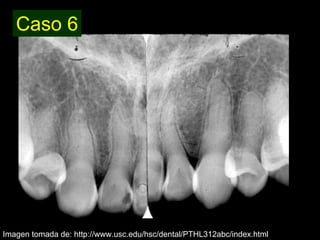

Dentinogénesis imperfecta es una condición genética que causa un disturbio en la formación de la dentina. Existen tres tipos principales. El tipo I se asocia con osteogénesis imperfecta. El tipo II solo afecta la dentina y causa dientes amarillos o grises con atrición. El tipo III es raro y se encuentra en un área aislada de Maryland, con exposiciones pulpares frecuentes. Todos los tipos muestran características radiográficas como obliteración de cámaras y conductos,